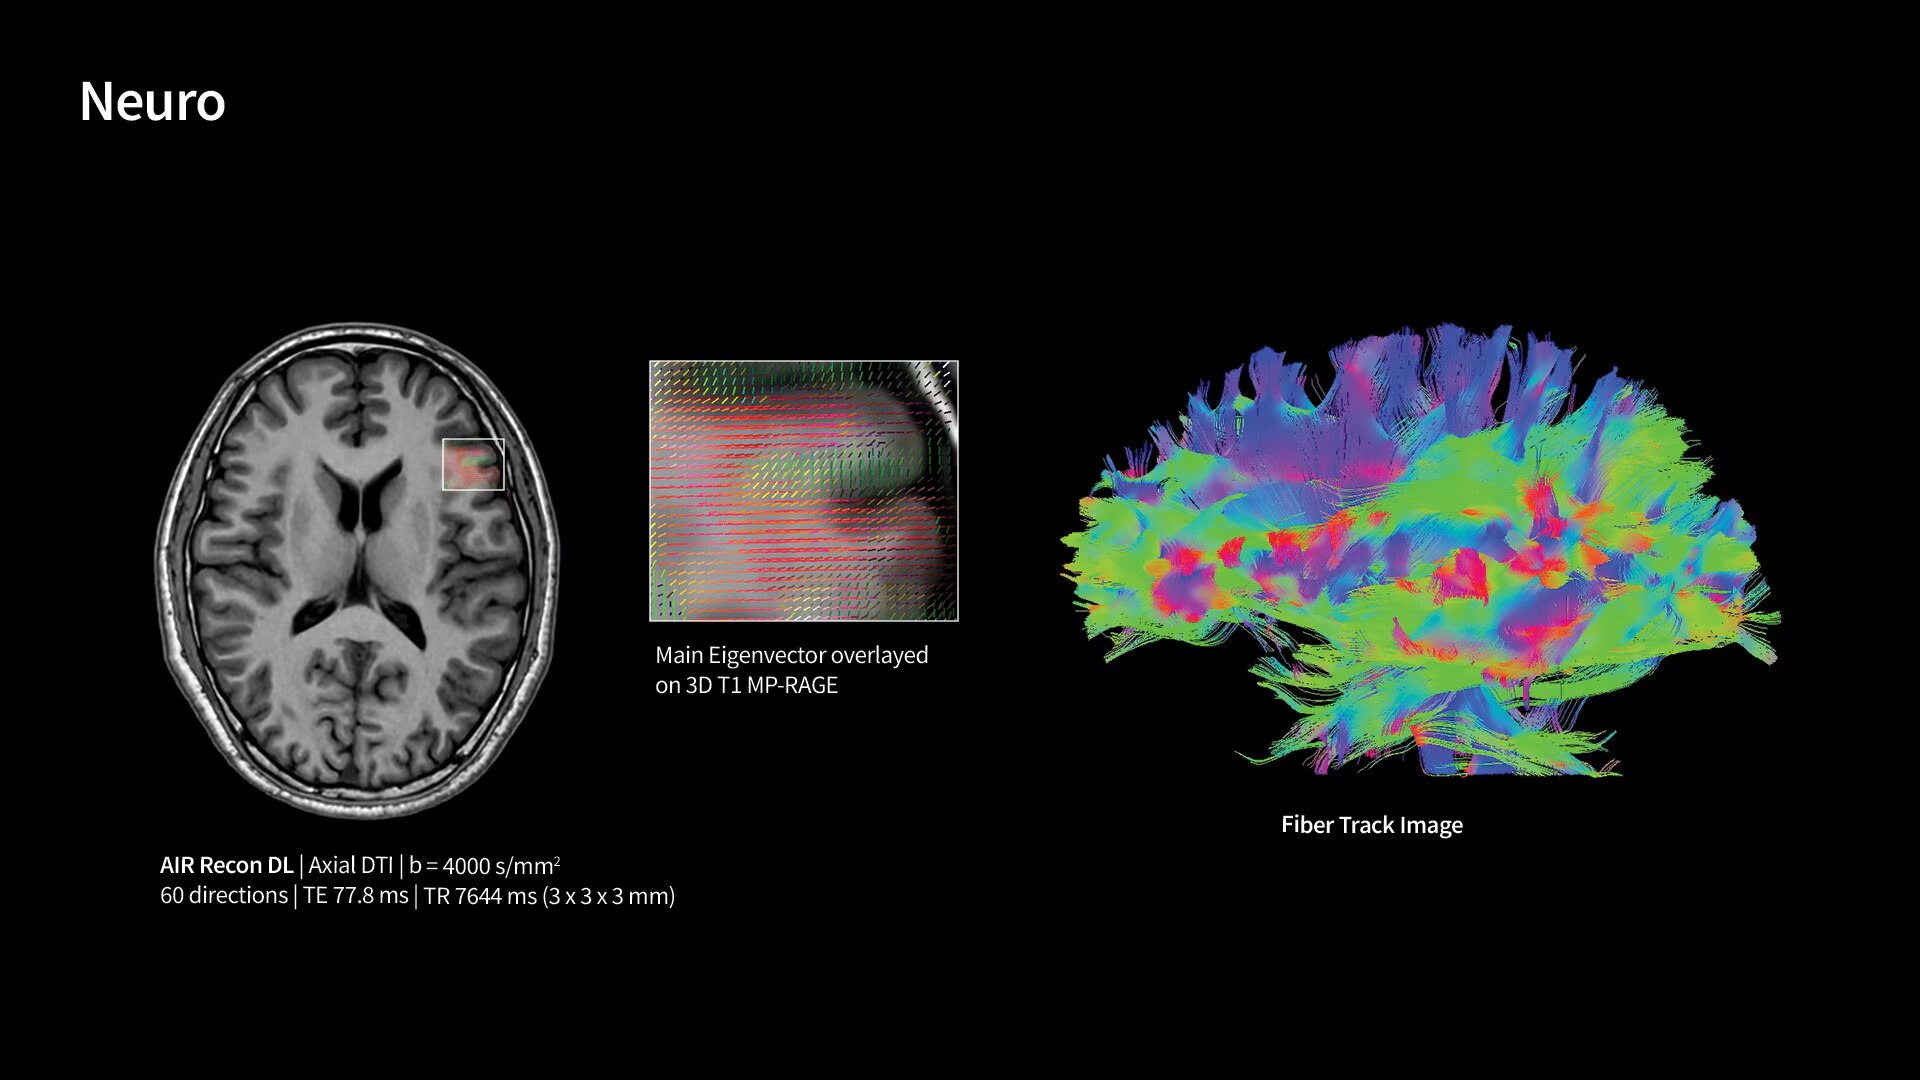

In oncological assessments, diffusion imaging is a critical clinical indicator. SIGNA Sprint offers clearer diffusion, reduced distortion and improved SNR.¹

Within cardiovascular diseases, the functional assessment of the heart is an essential imaging application. SIGNA Sprint is powered by built-in AI technologies—Sonic DL™, AIR Recon DL and AIR x™—enabling high-quality imaging even in the most demanding anatomies.

With GE HealthCare's comprehensive suite of deep-learning solutions integrated into SIGNA Sprint, you can unlock the full potential of your MRI system. No need for complicated patient setups or imaging protocols. The exceptional intelligence of our AI solutions offer multiple benefits, with AIR Recon DL giving pin-sharp images, Sonic DL accelerating scans up to 12x, and AIR x enabling automated slice placement. All helping to enhance your department’s workflow efficiency, increase patient throughput, and get the diagnostic clarity you need, faster.¹ Meaning you can spend more time on what truly matters—personalized patient care, enabling optimized treatment plans and treatment response monitoring—ultimately, supporting better clinical outcomes.